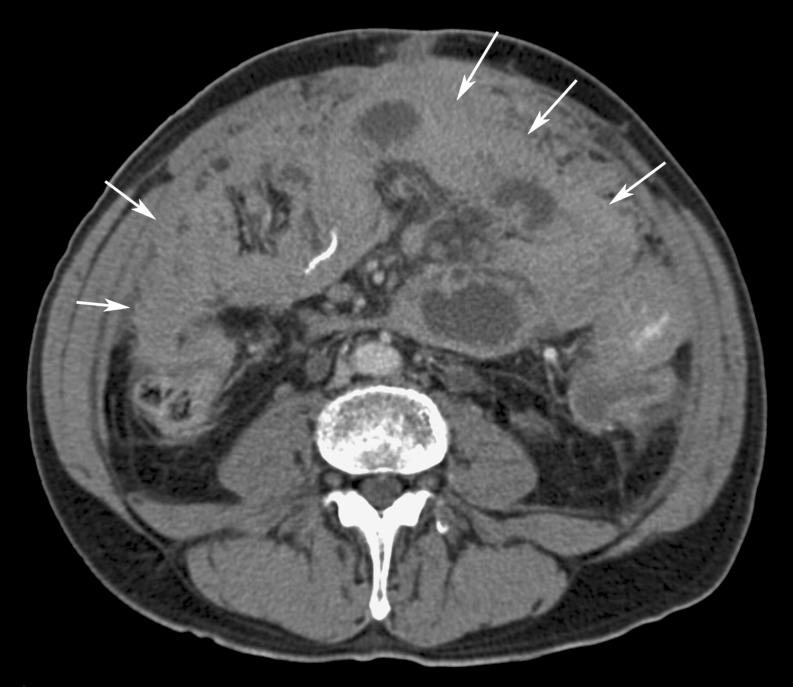

Omental cakes typically are associated with ovarian carcinoma, as this is the most common malignant aetiology. Nonetheless, numerous other neoplasms, as well as infectious and benign processes, can produce omental cakes. METHODS: A broader knowledge of the various causes of omental cakes is valuable diagnostically and to direct appropriate clinical management. RESULTS: We present a spectrum of both common and unusual aetiologies that demonstrate the variable computed tomographic appearances of omental cakes. CONCLUSION: The anatomy and embryology are discussed, as well as the importance of biopsy when the aetiology of omental cakes is uncertain.